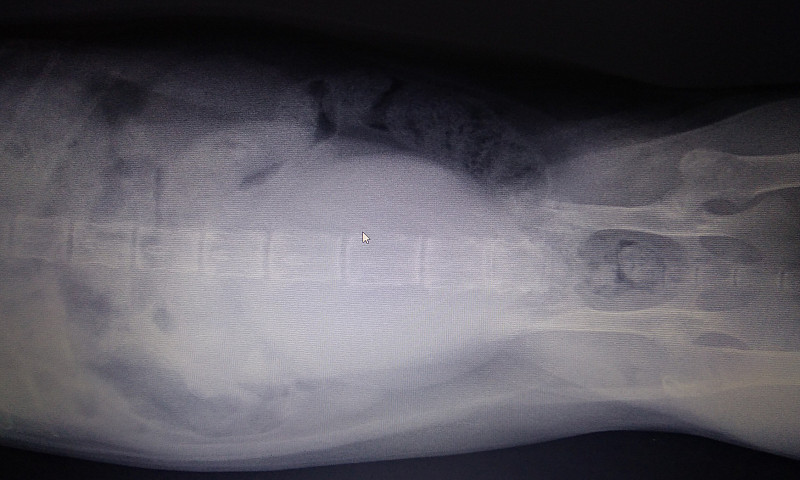

13.10.18 был сделан рентген. Там врач увидела перелом. Сказала нужна операция. И выписала травматин, анальгивет и корм мобилити. Уколы были проставлены один раз там же в клинике.

Снимки также были отправлены по вот сап и показаны 2-ум другим врачам один ничего не увидел. другой увидел смещение.

У котика кальций к нулю движется. Кости на снимке практически сливаются с мягкими тканями и вряд ли это только из-за качества снимка.